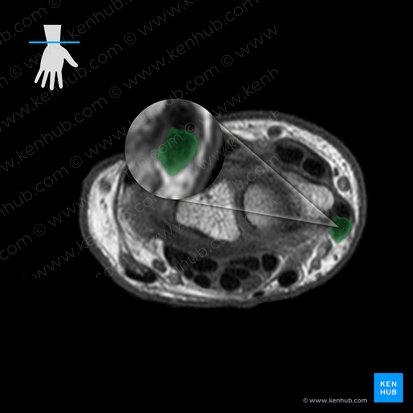

Abductor pollicis longus tendon then passes beneath the extensor retinaculum. In doing so, it traverses the first dorsal (extensor) compartment of the retinacular space. Once inside the dorsum of the hand, the tendon splits into two slips that insert onto the base of first metacarpal and trapezium bones, respectively. Some fibers may also insert into surrounding structures; opponens pollicis, abductor pollicis brevis and the fascia of thenar eminence.

The muscle belly of abductor pollicis longus lies in the distal half of the posterior forearm. It is found deep to extensor digitorum and lateral to extensor pollicis longus muscle, while its tendon is located lateral to the tendon of extensor pollicis brevis. The posterior interosseous nerve and artery course between the abductor pollicis longus and extensor digitorum, passing over abductor pollicis longus’ superficial surface.

The tendon of abductor pollicis longus forms the lateral border of the anatomical snuffbox. This is a triangular space found at the base of the thumb, distal and posterior to the styloid process of radius. The anatomical snuffbox is traversed by the neurovascular structures of the hand; the superficial branch of the radial nerve, the radial artery and cephalic vein. The margins of this space are completed by extensor pollicis longus (medial) and brevis (lateral), while the floor is comprised by the scaphoid and trapezium bones.